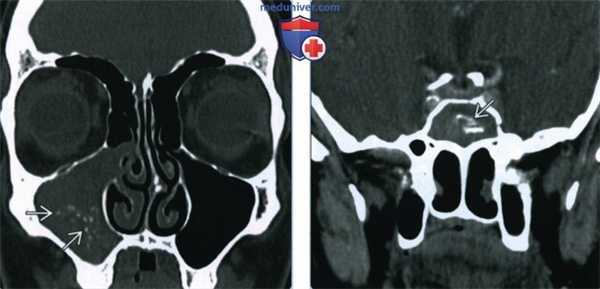

(Слева) При корональной КТ в костном окне определяются классические признаки мицетомы правой верхнечелюстной пазухи. Пневматизация пазухи снижена, но она не вздута. В пазухе визуализируется материал смешанной плотности (грибки и кальцинаты).

(Справа) При корональной КТ с КУ у пациента с мицетомой сфеноидальной пазухи визуализируются множественные кальцинаты в грибковом шаре. Пневматизация пазухи снижена, надкостница слегка утолщена, однако пазуха не вздута.

2. КТ при мицетоме пазух:

• КТ с КУ:

о Утолщенная слизистая оболочка может накапливать контраст

• «Костная» КТ:

о Снижение пневматизации или фокальное образование в просвете пазухи

о Центральная зона высокой плотности ± кальцинаты

о Хронические мукопериостальные изменения могут быть минимальными